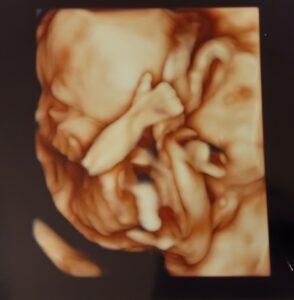

妊娠20週目の健診で映った「いいね」サイン

今回のエコー写真は、3回目の妊婦健診で撮影されたもので、この日はちょうど妊娠20週目。お腹の赤ちゃんの成長に期待がふくらむタイミングでもあります。

そんな中、画面に映し出されたのは、まるで「大丈夫だよ」と伝えるかのような、親指を上げた“いいね”のポーズ。

思わず笑ってしまうほど可愛い姿で「緊張がほぐれました」とママさんは当時の気持ちを振り返ります。